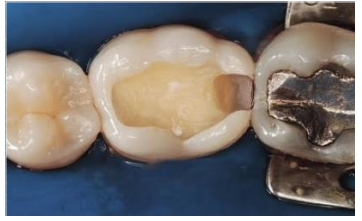

Observe a imagem abaixo:

Assinale a alternativa que apresenta a classificação da cavidade dentária presente na imagem: